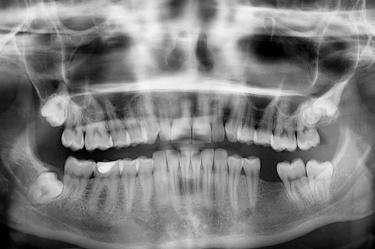

En la cuenta @archiebeshort, el joven explica que al ver esto quedó en shock y lo primero que le vino a la mente es que sus dientes se estaban pudriendo, pero lo más aterrador fue que no solo sus muelas de juicio están negras, sino que todo su cráneo, e incluso su esqueleto entero son de ese color.

"Me salió la muela del juicio y estaba negra, y yo estaba como 'Dios mío, mis dientes se están pudriendo… y resulta que mi mandíbula está negra, y probablemente el resto de mi cráneo y la mayoría de mis huesos, lo están también, según mi médico".

Archie también explicó qué fue lo que ocasionó esta condición en sus huesos y alertó que, en ciertas circunstancias excepcionales, pueden volverse negros.

De acuerdo con el joven, esto pudo haber ocurrido debido a que, en cuando estudiaba en la escuela secundaria, tomó minociclina, un antibiótico de tetraciclina, para tratar el acné de su rostro.

Es un trastorno denominado alcaptonuria que conduce a ocronosis. La deficiencia enzimática que produce provoca la acumulación de ácido homogentísico (HGA) a una velocidad 2000 veces superior a la normal.

El HGA se une al cartílago, al hueso y a los pigmentos, volviéndolos negros, de ahí el nombre popular de enfermedad del hueso negro.

A pesar de que se escucha bastante perturbador, al parecer se trata de un padecimiento benigno y no se asocia con necrosis o muerte del tejido, por lo que este joven podrá tener una vida completamente normal.